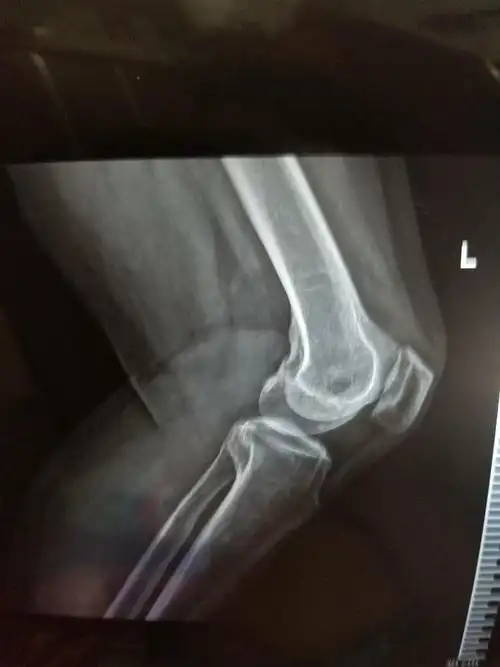

膝盖骨刺,骨质增生